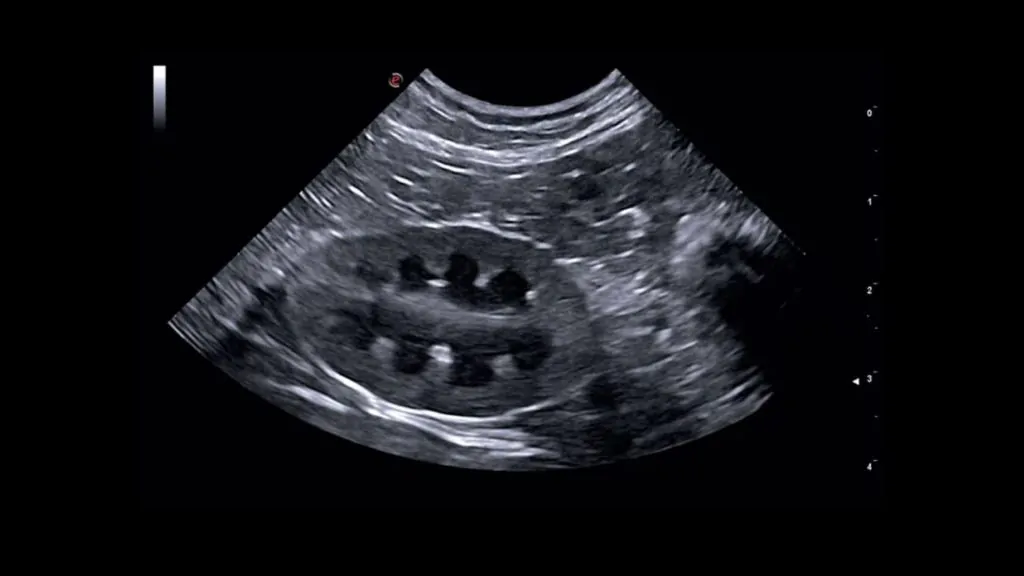

USG incelemesi genellikle evcil hayvan masada yatarken yapılır. Veteriner hekim, incelenecek bölgeye ultrason probunu yerleştirir ve probun hareketiyle ses dalgaları dokulara gönderilerek ekranda siyah-beyaz gerçek zamanlı görüntüler elde edilir.

ABDOMEN ULTRASONOGRAFİSİ

Abdomen ultrasonografisi, karın bölgesindeki organ ve yapıların değerlendirilmesinde kullanılan temel görüntüleme yöntemlerinden biridir. Aşağıdaki yapılar incelenebilir:

Abdomen USG’de Sık Değerlendirilen Yapılar